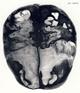

Gall, F. J. (1818). Anatomie et physiologie du système nerveux en général, et du cerveau en particulier, Avec des observations sur la possibilité de reconnoître plusieurs dispositions intellectuelles et morales de l´homme et des animaux, par la configuration de leurs têtes.

Librairie Grecque-Latine-Allemande, Vol. 3, I-XXXV u. 1-379 100 planches.